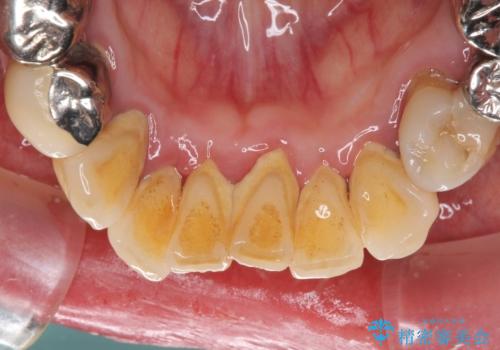

- 歯茎からの出血、入れ歯、歯の欠損、デコボコの前歯などを気にして来院された患者様です。

大の歯科治療嫌いとのことでしたが、今回の治療を契機にしっかりと治療を行いたいとのことでした。

油断をするとすぐに汚れが溜まって歯肉が腫れてきてしまうため、今後も定期的なメインテナンスが重要となります。